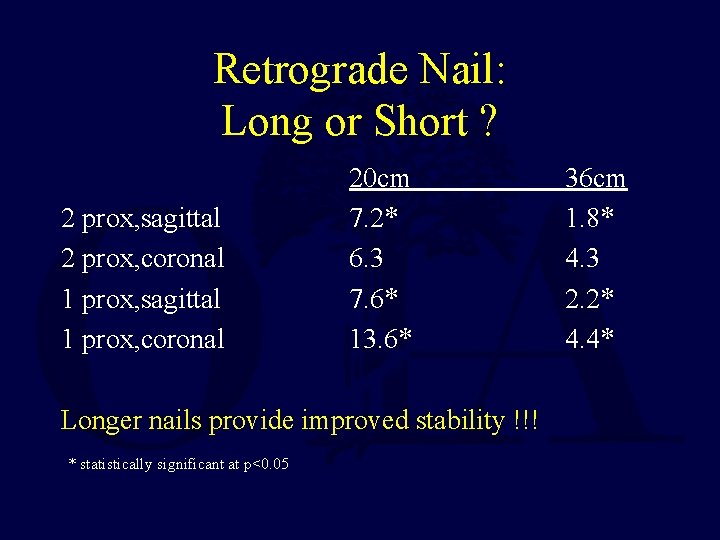

Retrograde Nail: Long or Short ? • 9 human matched cadaver femurs, gap model • 36 cm vs 20 cm • Coronal and sagittal testing • 75 Newtons applied in 3 point bending • Locked with 1 or 2 proximal screws

Retrograde Nail: Long or Short ? 2 prox, sagittal 2 prox, coronal 1 prox, sagittal 1 prox, coronal 20 cm 7. 2* 6. 3 7. 6* 13. 6* Longer nails provide improved stability !!! * statistically significant at p<0. 05 36 cm 1. 8* 4. 3 2. 2* 4. 4*